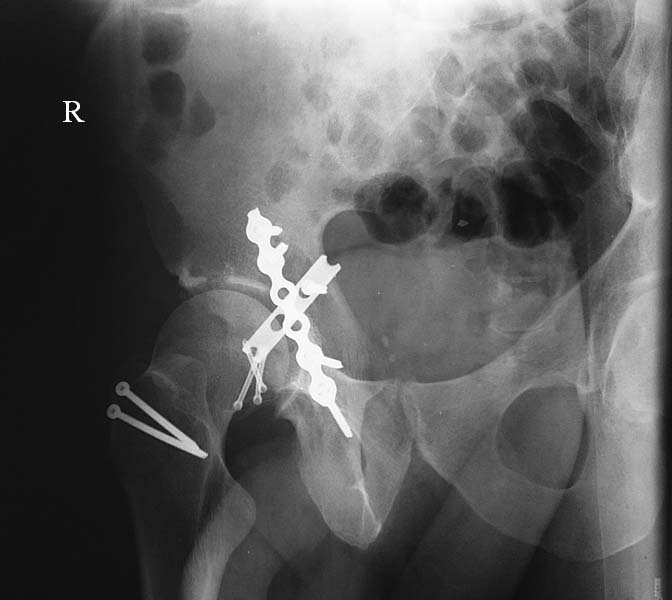

При поступлении выполнено закрытое вправление головки бедра, налажено

скелетное вытяжение. Контрольный рентген показал разницу в ширине

суставных щелей в сравнении с неповрежденной стороной. Сделали КТ,

которое подтвердило наличие внутрисуставного фрагмента задней стенки

вертлужной впадины и перелом нижне-медиального сегмента головки со

смещением (Pipkin IV).

Через 12 дней выполнен остеосинтез головки 3-мя самокомпрессирующими

винтами Герберта. Доступ Kocher-Langenbeck с флип-остеотомией большого

вертела и задним хирургическим вывихом головки бедра. Интерпонирующий

внутрисуставной фрагмент представлял собой лабрум с тонкой костной

пластинкой от заднего края впадины. Фрагмент извлечен и фиксирован

техникой spring-plate.